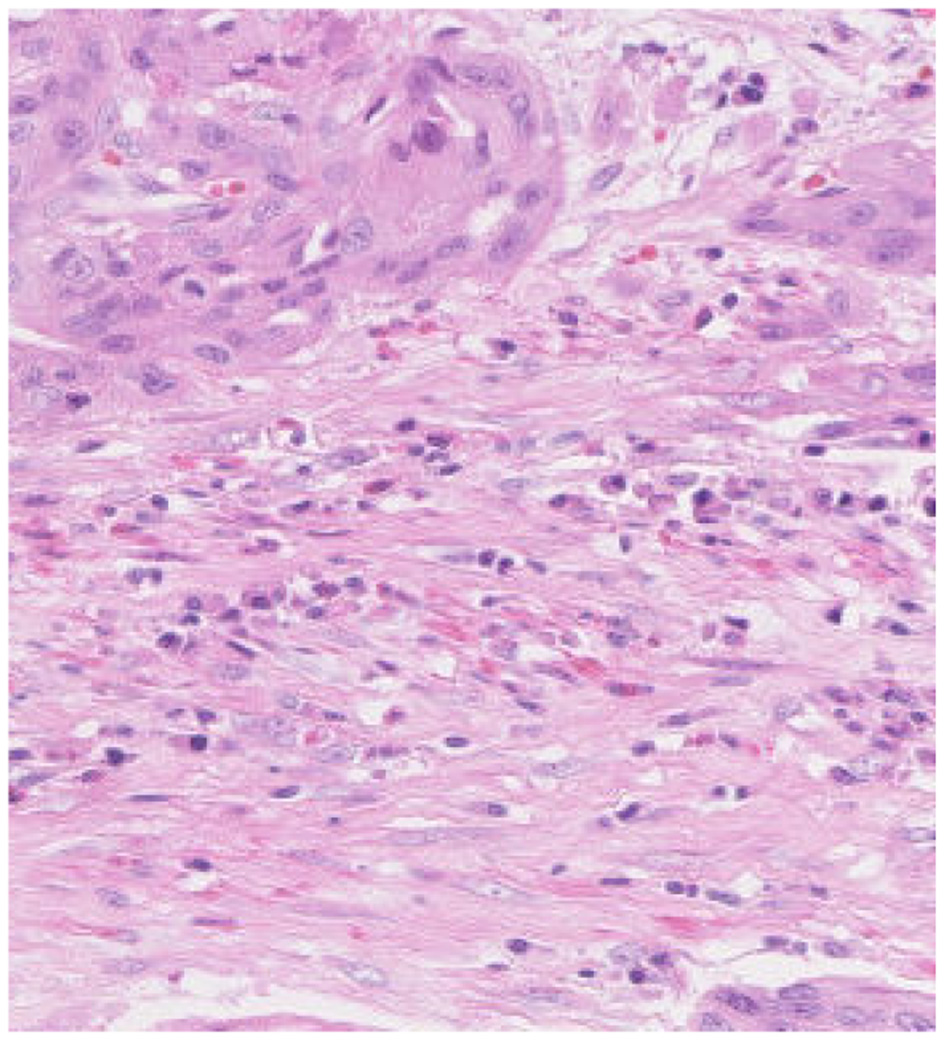

In histopathological studies, microscopic images play a crucial role in medical research, diagnosis, and treatment. In pathology, microscopic images of tissue sections offer detailed views of the internal structure and lesions of biological tissues. An example of a histopathological image is shown in Figure 1. These images are critical for disease diagnosis, pathology research, and decision making in medical practice. It can help doctors and researchers better understand and diagnose diseases (1). Ajay proposed a method to identify the extent of lymphocyte infiltration in histopathological images of breast cancer, offering a new quantitative approach for pathological assessment (2). Additionally, cellular images have wide-ranging applications in pathology. In clinical trials, cytological examination can detect abnormal cell morphology, including changes in cell size, nuclear morphology, and organelle structure, aiding in the early detection of lesions. For example, neutrophils with abnormal features are shown in Figure 2. These are hypersegmentation, D..ohle bodies and hypergranulation of neutrophil. It is usually used to diagnose a number of malignancies and leukaemias in the hematological system (3). Finally, micrographic techniques can be combined with methods such as fluorescent labeling. Thus, the localisation and distribution of biomolecules (e.g. proteins, nucleic acids, etc.) in cells and tissues can be observed and analyzed (4). In environmental science research, microscopic image can be used to observe microbial community structure, abundance and distribution. Through micrographic techniques to study the relationships of microbial diversity, ecological functions with environmental change. It provides effective technical means and important data support for the study of environmental microbial ecology. For example, algae are good bioindicators for water pollution assessment. Using micrographic techniques it is possible to measure changes in algal species and abundance to identify changes in water quality and nutrient status (5).

Figure 1

Histopathologic image of intestines tissue sections observed under the microscope.